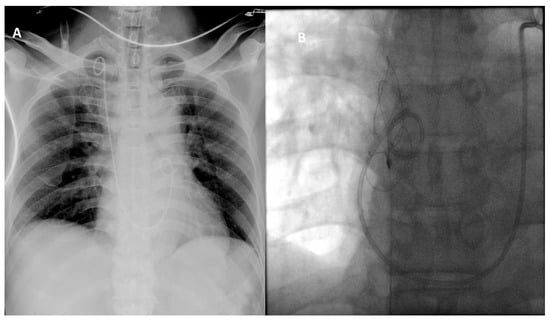

| Chang et al. (present study) | M/R/60 | Right heart | PNL (first-described) | Endovascular |